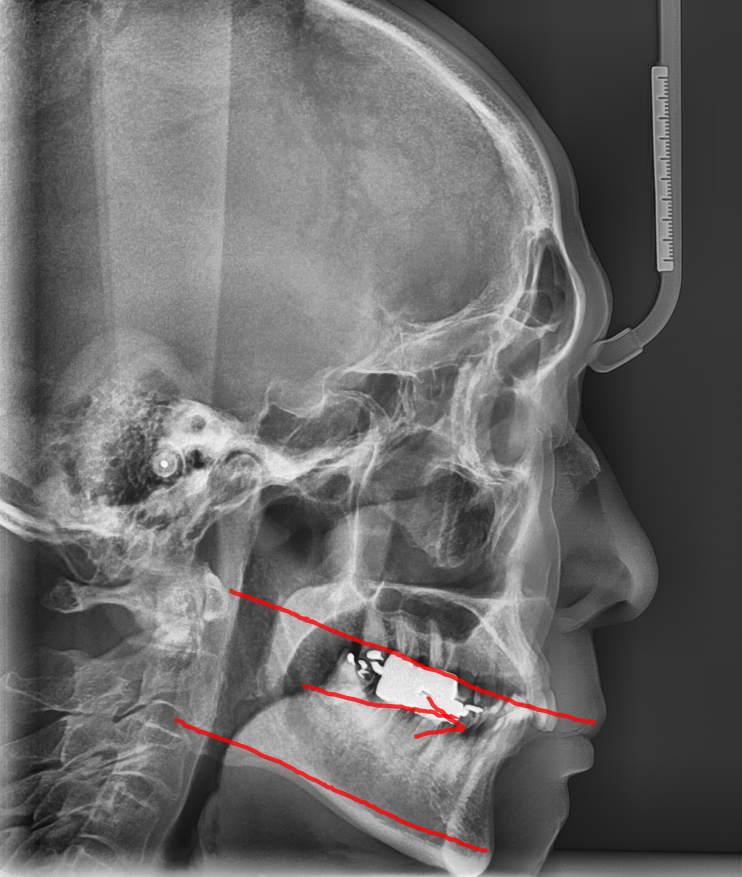

선 교정 후 임플란트가 원칙!!!

대부분의 경우, 교정을 먼저 진행하고

임플란트를 식립하는 것이 원칙입니다!!!

그 이유는 다음과 같습니다..

먼저 치아 교정의 원리를 생각해볼까요~?

치아를 움직여 배열을 맞춰주는 것이 치아 교정인데...

임플란트는 뼈에 식립하기 때문에 치아가 움직이지 않아요~

아무래도 교정에 제한이 생길 수 밖에 없겠죠?

(두가지 진료의 특성은 정 반대랍니다!)

때문에 교정을 먼저하여 필요한 공간을 만들거나

자연 치아의 위치를 최적에 위치로 만들어놓고

적절한 교합이 형성된 상태에서 임플란트를 심는걸 추천드려요!!